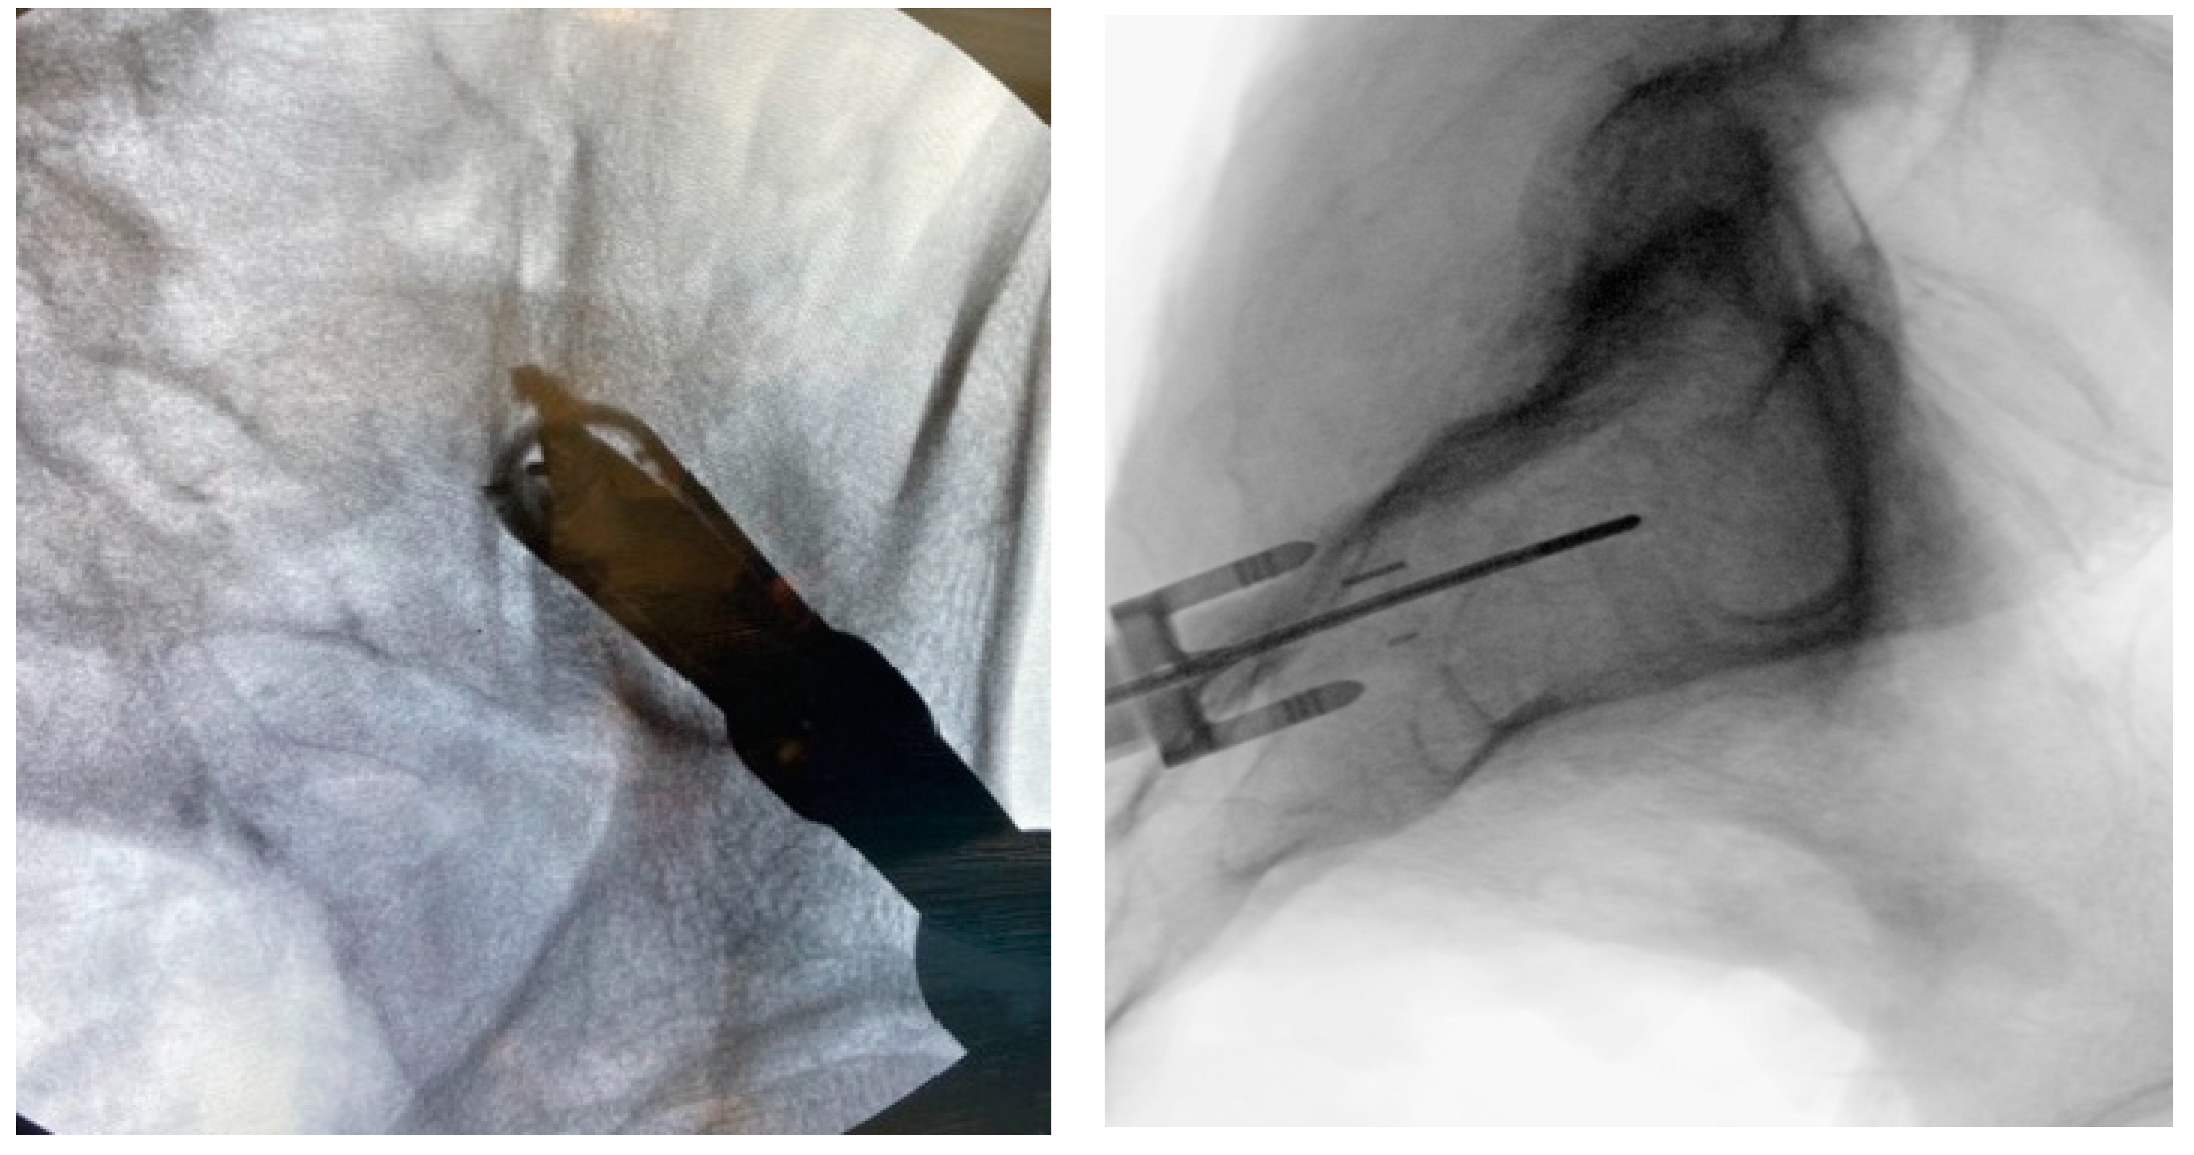

Figure 7. Proper implant insertion and placement showing the implant going through the ilium, across the SI joint, and into the sacrum.

Preprints 71623 g007

3.3.8. Implant Insertion

Once the Docking Washer has been firmly seated in the inferior aspect of the ilium and proper trajectory has been obtained, the PsiF™DNA implant is inserted down the Docking Washer Tower. Once the distal tips of the implant make contact with the ilium, ventral pressure is applied as the inserter is turned clockwise. The self-tapping, autograft harvesting implant will advance through the ilium, across the SI joint and into the sacrum (Figure 7). When final placement is achieved, the base of the implant will lock in the Docking Washer. The base of the Docking Washer provides added safety from foraminal and ventral cortical breech.